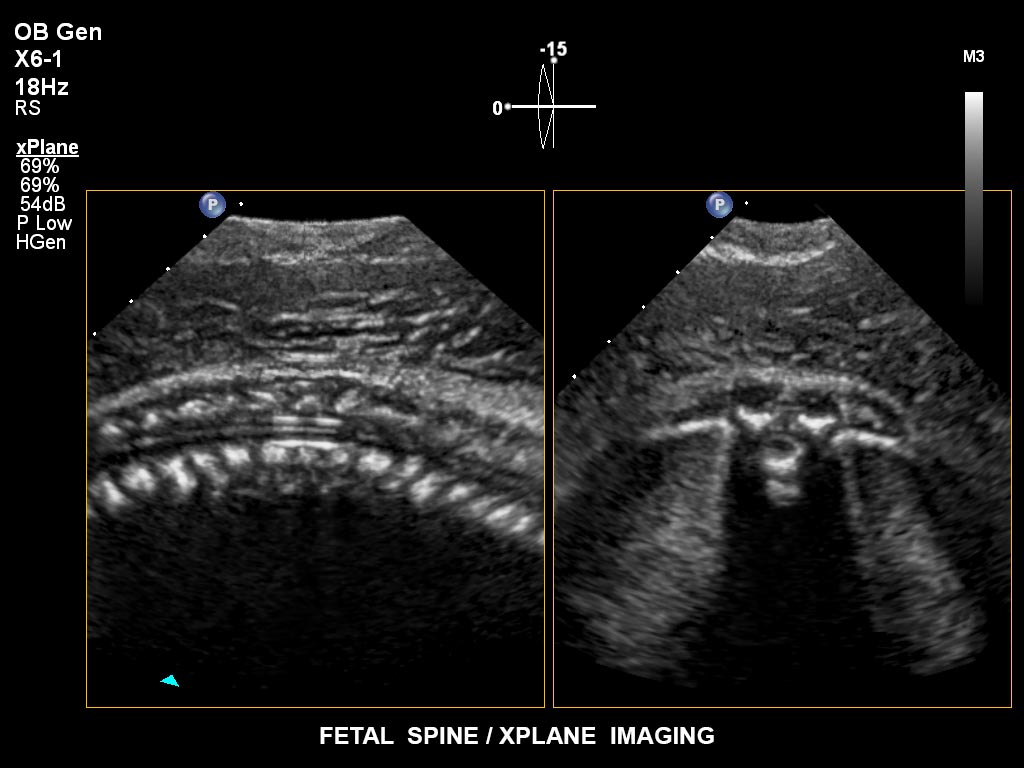

• X6-1 PureWave-xMATRIX Schallkopf für diagnostische Anforderungen, die über die 2D-Bildgebung hinausgehen, setzt mit PureWave neue Maßstäbe u.a. bei der Live-Volumenbildgebung und Live-Bildgebung in zwei Ebenen gleichzeitig